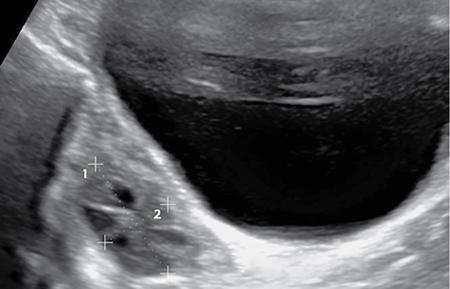

IMAGING ANATOMY OF MALE REPRODUCTIVE SYSTEM Ganesh Rajagopal The male reproductive system is formed by testes, ejaculatory ducts, seminal vesicles (SVs), prostate and penis. Various diagnostic imaging modalities like ultrasound (US), computed tomography (CT), magnetic resonance imaging (MRI) and positron emission tomography (PET) are helpful in the diagnostic evaluation of male reproductive system. Various indications for imaging may include acute scrotum (testicular torsion, trauma and epididymo-orchitis), scrotal swelling (hydrocele, spermatocele, idiopathic scrotal wall oedema and scrotal abscess) and infertility. US and MRI are the commonly used imaging modalities in male reproductive system which complement each other. CT is not very useful due to poor contrast resolution. Ultrasound imaging (US) with a high-frequency linear (7.5–10 MHz) transducer probe has become the imaging modality of choice for scrotal evaluation. Scrotal US is an excellent imaging modality as it can demonstrate abnormalities in testis as well as in paratesticular structures. Scrotal wall is formed by the skin, superficial fascia, dartos muscle, the external spermatic fascia, cremasteric fascia and the internal spermatic fascia. The scrotum is divided into two cavities by a median raphe. This multilayered scrotal wall is poorly delineated in US and MRI, it is typically hypointense on both T1- and T2-weighted images. Testes are paired organs, located normally in scrotal sac, suspended by the spermatic cords. Each testis is examined in orthogonal transverse and longitudinal planes, with both grey scale and colour Doppler modes, to assess its volume and blood flow. Volume of testis is calculated by length × height × width × 0.71. A total volume (both testes) of >30 mL and a single testicular volume of 12–15 mL is generally considered normal for adults. Testes are supplied by the testicular arteries, which arise from the aorta and enter the spermatic cord at deep inguinal ring to reach the upper pole of testis. Pampiniform plexus of veins surrounds the testis and appears as a serpiginous tubular structure posterior to it, measuring >2–3 mm in diameter. Testes are oval shaped, with homogeneous echotexture on grey scale US. Along with the epididymis, they are surrounded by an echogenic capsule, known as the tunica albuginea. Tunica albuginea is covered by tunica vaginalis, which is a remnant of the processus vaginalis and both represent closed sac of peritoneum with two layers. This tunica albuginea is seen extending into posteromedial testis and form the mediastinum testis (Fig. 11.2.1.1), which consists of ducts, nerves and blood vessels. The mediastinum testis is seen as a thin echogenic band. Rete testis is formed by the convergence of seminiferous tubules, seen as a hypoechoic area adjacent to mediastinum testes. The epididymis is a comma-shaped, elongated structure placed at the posterior border of the testis, which drains the efferent ductules (Fig. 11.2.1.2). It has head, body and tail. The head overlies the superior pole of the testis and is isoechoic or slightly hyperechoic whereas, the body and tail are located behind and along the inferior pole and are usually isoechoic. The tail of the epididymis continues into vas deferens (VD), which along with the nerves, lymphatic and vascular structures, forms the spermatic cord (Fig. 11.2.1.3). The spermatic cord appears as an echogenic band in the inguinal canal. The normal adult testis is a homogeneous oval structure that appears hyperintense on T2-weighted sequences and hypointense–isointense on T1-weighted images (Fig. 11.2.1.4). The tunica which surrounds the testis is hypointense T1- and T2-weighted sequences. Epididymis is isointense on T1-weighted images but hypointense on T2-weighted images compared to testis (Fig. 11.2.1.5). Both testicles and epididymis enhance after intravenous administration of gadolinium (Gd) MR contrast agents. Prostate, though visualized by transabdominal scan is better assessed by transrectal high frequency (7.5–10 MHz) ultrasound transducer (TRUS) with patient in left lateral decubitus position. The prostate gland is divided into the anterior fibromuscular stroma (devoid of glandular tissue), transition zone, central zone, periurethral zone and peripheral zone. The base of the prostate is located superiorly and contiguous with the bladder neck whereas, the apex of the prostate is located at the inferior aspect continuous with the striated muscles of the urethral sphincter. The neurovascular bundle is seen to course near the posterolateral aspect of prostate, which is a preferential route of tumour spread. The prostate appears as a cone-shaped organ and shows uniform low echogenicity (Fig. 11.2.1.6). The outer gland (central and peripheral zones) is generally more echogenic than the inner gland. The transition and central zones of the prostate have similar MR signal intensity and cannot be differentiated, hence, are collectively referred as the central gland. On T2-weighted MR images, the normal peripheral zone is homogeneously hyperintense, whereas the central gland tissue is typically hypointense or isointense compared to the skeletal muscle (Fig. 11.2.1.7). The capsule and the anterior fibromuscular stroma appear hypointense on T2-weighted MR images. The SVs are seen as septate tubular cystic structures, appearing uniformly anechoic in US, above the prostate with distal portion of VD is seen medial to it. The duct of SV and VD joins to form the ejaculatory duct, which drains into the prostatic urethra via verumontanum. SVs show ‘bow-tie’ appearance in transversal scans, and a club or tennis-racket shape in longitudinal scans (Fig. 11.2.1.8). On MR, SVs are seen as elongated fluid-containing structures with thin septa, which is hypointense on T1 and hyperintense on T2-weighted MR images (Fig. 11.2.1.9). The VD is seen as a tubular structure with low signal intensity in both T1- and T2-weighted images, on either side. The dilated distal portion of VD (ampulla), appears hyperintense on T2-weighted images, similar to that of the SV due to the fluid content (Fig. 11.2.1.10). The penis, being a superficial organ, is usually examined with US, although MRI is reserved as problem solving modality. The penile body contains two paired muscles – corpora cavernosa and a corpus spongiosum. The former performs as a main erectile body while the latter contains the penile urethra (Fig. 11.2.1.11). Dartos fascia forms the outer layer and the Buck fascia forms the inner layer, which contain the deep dorsal vein (DDV) and a paired dorsal neurovascular bundle. The corpus spongiosum and corpora cavernosa are of high signal intensities on T2-weighted MR images and intermediate-low signals on T1-weighted MR images. The tunica albuginea being a fibrous sheath, surrounds all the three muscles, is hypointense on all sequences (Fig. 11.2.1.12). IMAGING ANATOMY OF FEMALE REPRODUCTIVE SYSTEM Saranya The female reproductive system comprises of uterus, cervix, fallopian tubes, ovaries, vagina and vulva. Ultrasonography (transabdominal and transvaginal) is the primary imaging modality of choice for imaging the female pelvis. Computed tomography (CT) is less often used for pelvic imaging. It provides a quick and systematic overview with coverage of the abdomen in the same session. Hence, CT is well suited for staging pelvic cancers and for imaging gynaecologic and nongynaecologic diseases presenting with acute abdominal pain. Pelvic anatomy is well demonstrated by magnetic resonance imaging (MRI). The contrast resolution of T2-weighted images form the basis for superb tissue characterization of MRI. Uterus is a thick-walled fibromuscular organ composed of myometrium and endometrium. It has two major divisions, namely, the body (corpus) and cervix. The fundus lies above the ostia of fallopian tubes. The normal uterus measures between 5 and 9 cm in length and is in an anteverted position, in relation to the urinary bladder. The myometrium shows three layers on USG, a compacted thin, hypoechoic inner layer forms subendometrial halo, a thicker, homogenously echogenic middle layer and a thinner, hypoechoic outer layer (peripheral to arcuate vessels). The appearance of the endometrium varies with the phase of the menstrual cycle. It appears as a thin echogenic line early in the proliferative phase and shows hypoechoic thickening (4–8 mm) as proliferative phase progresses. It shows a triple layer (sandwich or trilaminar) appearance in the mid cycle and may measure up to 12–16 mm. During secretory phase after ovulation, the layers are seen hyperechoic due to the increasing complexity of glandular structure and secretions (Fig. 11.2.2.1). Postmenopausally, the endometrium decreases in thickness. Endometrial thickness of 5 mm is taken as cut-off. Women on hormonal therapy acceptable endometrial thickness is up to 8 mm. Three-dimensional US permits multiple views to be reconstructed from a single sweep through the uterus. Sonohysterogram is the study of choice for detailed evaluation of the endometrial cavity pathologies. The cervix begins at the inferior narrowing of the uterus (isthmus) at the internal os, which is identified by the entrance of uterine vessels. It has supravaginal and vaginal portions. It is 3–4 cm long and shortens after childbirth. In premenarche women, cervix is larger than corpus, forming approximately 2/3 of the uterine mass. During menarche, there is preferential growth of the corpus and in nulliparous women, corpus and cervix are roughly equal, whereas in parous woman, corpus forms approximately 2/3 of the uterine mass. Uterus is an extraperitoneal organ. The peritoneum extends over urinary bladder dome to anterior uterus, forming anterior cul-de-sac (vesicouterine pouch) and posteriorly, the peritoneum extends more inferiorly to the upper portion of vagina, forming the posterior cul-de-sac (pouch of Douglas, rectouterine pouch), which forms the most dependent portion of the female pelvis. Supporting ligaments of the uterus comprise mainly of broad ligaments, which extend laterally to the pelvic wall and round ligaments, which arise from uterine cornu near fallopian tubes to course anteriorly, pass through the inguinal canal to insert on the labia majora. Connective tissue thickening at the base of the broad ligament forms the uterosacral ligaments posteriorly, cardinal ligaments laterally and vesicouterine ligaments anteriorly. CT examination displays the uterus as a triangular or ovoid soft tissue structure behind the urinary bladder (Fig. 11.2.2.2). Following the administration of intravenous contrast, there is enhancement of myometrium that helps to delineate the endometrium. The vagina, cervix and corpus can be differentiated by morphological characteristics and enhancement pattern. The uterine corpus is typically triangular, whereas cervix is more rounded. The vagina has an appearance of flat rectangle at the level of fornix. The broad ligament and round ligaments are seen coursing laterally and anteriorly, respectively. The main source of vascular supply to uterus is from the uterine arteries. The uterine arteries pass within the broad ligament to enter the uterus, adjacent to the lateral fornices. The uterine artery passes over the ureter at the level of the cervix. Then it courses superiorly, along the lateral margin of the uterus and anastomoses with the ovarian artery. Uterine arteries give rise to arcuate arteries, which run in the outer third of myometrium. Radial arteries extend through the myometrium, which terminate as spiral arteries in the endometrium. The venous system parallels the arterial system, forms a complex venous network in the parametrium and drains to the iliac veins. Middle and lower thirds of the uterus are drained by obturator, parametrial and paracervical lymph nodes. Lymphatic drainage from the upper corpus and fundus goes to the common iliac and paraaortic lymph nodes. MRI provides a more comprehensive view of the uterine anatomy. On MRI, the uterus and cervix show uniform low to intermediate signal on T1-weighted images. On T2-weighted images, uterus shows three distinct zones, namely high signal endometrium, low signal junctional zone and intermediate signal myometrium (Fig. 11.2.2.3). The normal thickness of the junctional zone varies from 2 to 8 mm. A thickness of 9 to 12 mm is equivocal and greater than 12 mm is abnormal. Both endometrium and junctional zone become thin with oral contraceptive intake. Endometrial atrophies and the junctional zone is absent in postmenopausal women. The endocervical canal shows high signal on T2-weighted images, whereas cervical stroma shows low signal, contiguous with the junctional zone. An outer layer of intermediate signal smooth muscle is present. Nabothian cysts representing obstructed, mucous secreting glands are commonly seen as low signal on T1-weighted images and high signal on T2-weighted images. Parametrium shows low to intermediate signal intensity on T1-weighted images and variable signal intensity on T2-weighted images. The round ligaments and uterosacral ligaments show low signal intensity, cardinal ligaments and associated venous plexuses show high signal intensity on T2-weighted images. Ovaries are located posterolateral to the body of the uterus between the uterus and the pelvic sidewall. The internal iliac vessels lie immediately posterior to the ovary. Exact position is variable due to the laxity in the ligaments, parity, uterine size and position. On USG, medulla of the ovaries is mildly hyperechoic compared to the hypoechoic cortex. Developing follicles appear anechoic (Fig. 11.2.2.4). Corpus luteum may have a thick, echogenic ring and haemorrhage is common.